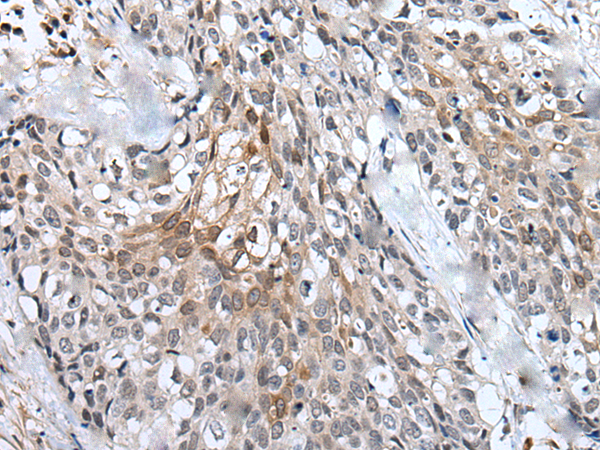

IHC positive control: |

Human lung cancer and human brain |

IHC Recommend dilution: |

20-100 |